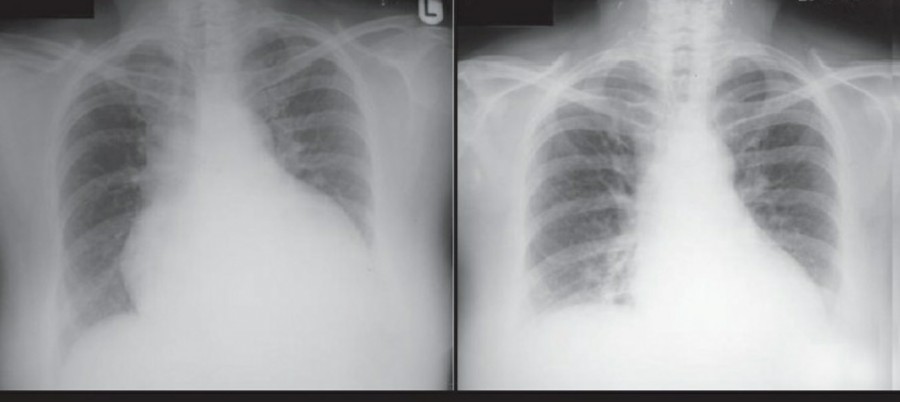

공기는 nondependent position으로 위치하므로, X ray상에서는 환자 자세에 따라 다르게 나타난다. Erect position에서 공기는 lung의 apicolateral surface에 위치하고 얇고 하얀 pleural line이 나타나며 그 뒤로 lung marking이 보이지 않는다.

하지만 pleural line 뒤로 lung marking이 존재한다고 해서 pneumothorax를 배제할 수 없다. Pneumothorax의 진단은 특히 parenchymal disease가 있을 때 진단하기 힘든데, 이는 compliance의 변화 때문에 collapse가 잘 안 되기 때문이다. Skin fold가 pneumothorax와 비슷하게 보이기도 한다.

중환자에서 pneumothorax의 진단은 종종 supine radiograph에서 내릴 수 있다. Supine position에서 공기는 anteromedial 방향으로 모이게 되는데, apical air collection이 있을 경우 large pneumothorax가 있음을 시사한다. 공기는 lung과 diaphragm 사이의 subpulmonic location에 trap 되어 있을 수도 있다. 공기가 costophrenic sulcus로 anterolateral extension 될 경우, 이 costophrenic sulcus의 radiolucency를 증가시키는데, 이를 deep sulcus sign이라고 한다. Subpulmonic pneumothorax의 다른 특징으로 diaphragm의 superior surface와 IVC 윗부분이 뚜렷하게 보일 수 있다.